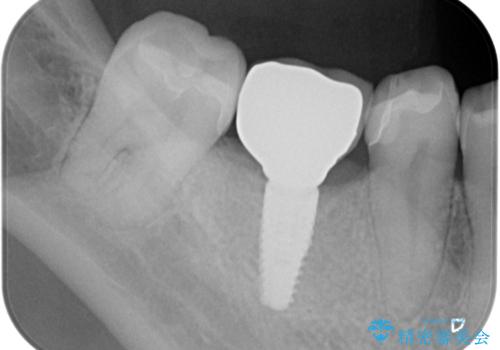

- 44万円(インプラント・チタンカスタムアバットメント・ジルコニアクラウン・仮歯)費用は治療当時の料金となります

安定し、長く使用できるようなインプラント治療を実践するため、骨の増成をインプラント埋入と同時に行いました。